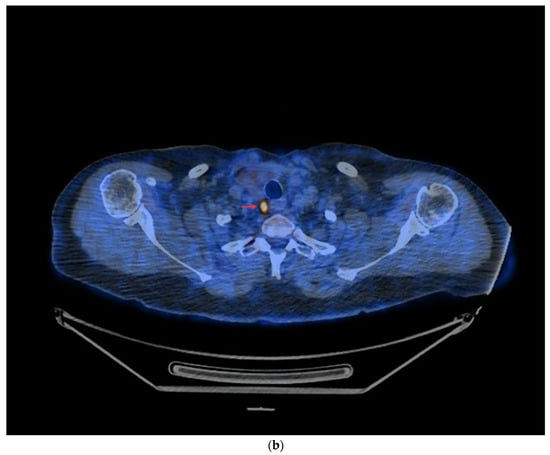

- In the case of potentially resectable lesions, the lesions were operated on after the FNA verification (Figure 3a,b).

Figure 3. PET/CT with [18F]FDG (a) Maximum-intensity projection (MIP). (b) Axial fusion projection. These show an example of the accumulation of the [18F]FDG in the left cervical lymph node (red arrow). The lesion was verified as being metastasized DTC using FNA and resected. The preoperative sTg concentration was 5.55 ng/mL. In the postoperative follow-up, the sTg concentration decreased to being undetectable (<0.04 ng/mL). - -